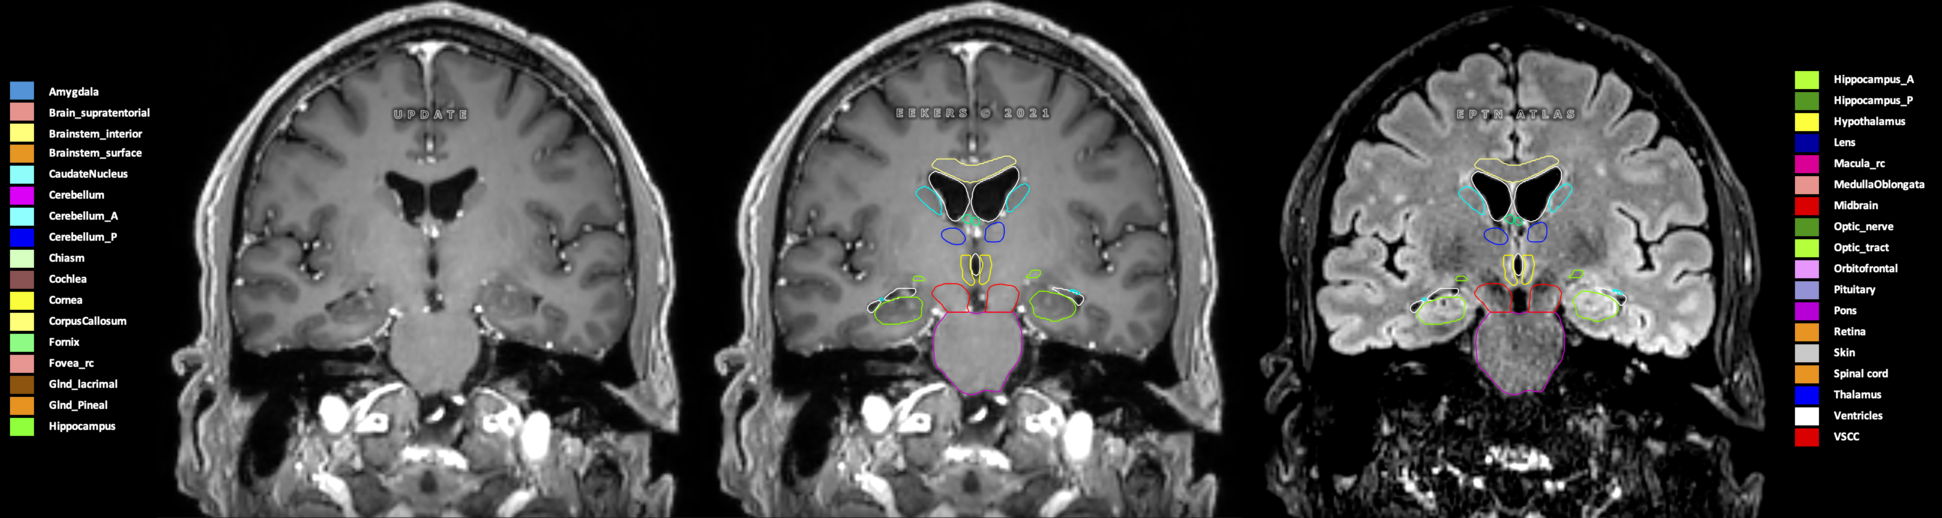

Eekers et al. have published an international neurological atlas for contouring of organs at risk in consensus with the European Particle Therapy Network (EPTN) in 2018 and an update in 2021. The purpose of this consensus atlas is to decrease inter- and intra-observer variability in delineating OARs relevant for neuro-oncology.

Included are all OARs known to be relevant for radiation-induced toxicity in neuro-oncology: brain, brainstem (midbrain, pons, medulla oblongata), chiasm, cerebellum (anterior & posterior), cochlea, cornea, hippocampus (anterior & posterior), hypothalamus, lens, lacrimal gland, optic nerve, pituitary, skin, and vestibular & semicircular canals. To further facilitate research on cognition, vision and radiological changes after irradiation of the brain, potential clinically-relevant OARs are included: amygdala, caudate nucleus, cerebellum (anterior & posterior), corpus callosum, fornix, macula, optic tract, orbitofrontal cortex, periventricular space (PVS), pineal gland, and thalamus.

Three-dimensional delineation of the 25 consensus OARs for neuro-oncology are shown on CT (WW/WL 120/40, 3000/600), 3T MR images, (T1Gd, T2FLAIR 1mm) and 7T MR (MP2RAGE 0.7 mm). All are presented in transversal, sagittal and coronal view.